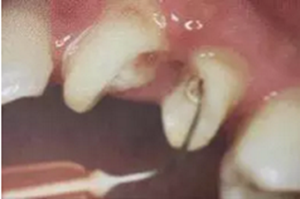

2. 清除根管壁殘留物

根管壁殘留物的存在直接影響纖維樁的粘接和固位,這也是導(dǎo)致纖維樁脫落的主要原因。

(根管內(nèi)殘留物)

個(gè)人見解:必要的情況下先開闊根管口建立一定的視角后,慢速手機(jī)上G鉆為引導(dǎo)鉆,由號(hào)遞增引導(dǎo)開闊通路;P鉆預(yù)備樁道,同樣需要由小向大號(hào)遞增,直到選擇好適合的號(hào)預(yù)備到規(guī)定測(cè)量的深度即可,再配合纖維樁系統(tǒng)中各型號(hào)纖維樁所匹配的樁道鉆,預(yù)備、修整成與纖維樁相適應(yīng)的樁道。

預(yù)備后根管壁上會(huì)不同程度的牙膠和封閉劑等殘留物,所以樁道預(yù)備前后建議X線片輔助檢查預(yù)備深度等情況,而殘留物也會(huì)很清晰地顯現(xiàn)。

根管銼去除殘留物,很難去除干凈,而備取樁道時(shí),禁止使用牙膠溶解劑(如:丁克除、氯仿)等有機(jī)溶劑去除殘留物,以防破壞根尖區(qū)牙膠的封閉和防止附著根管壁影響粘接。